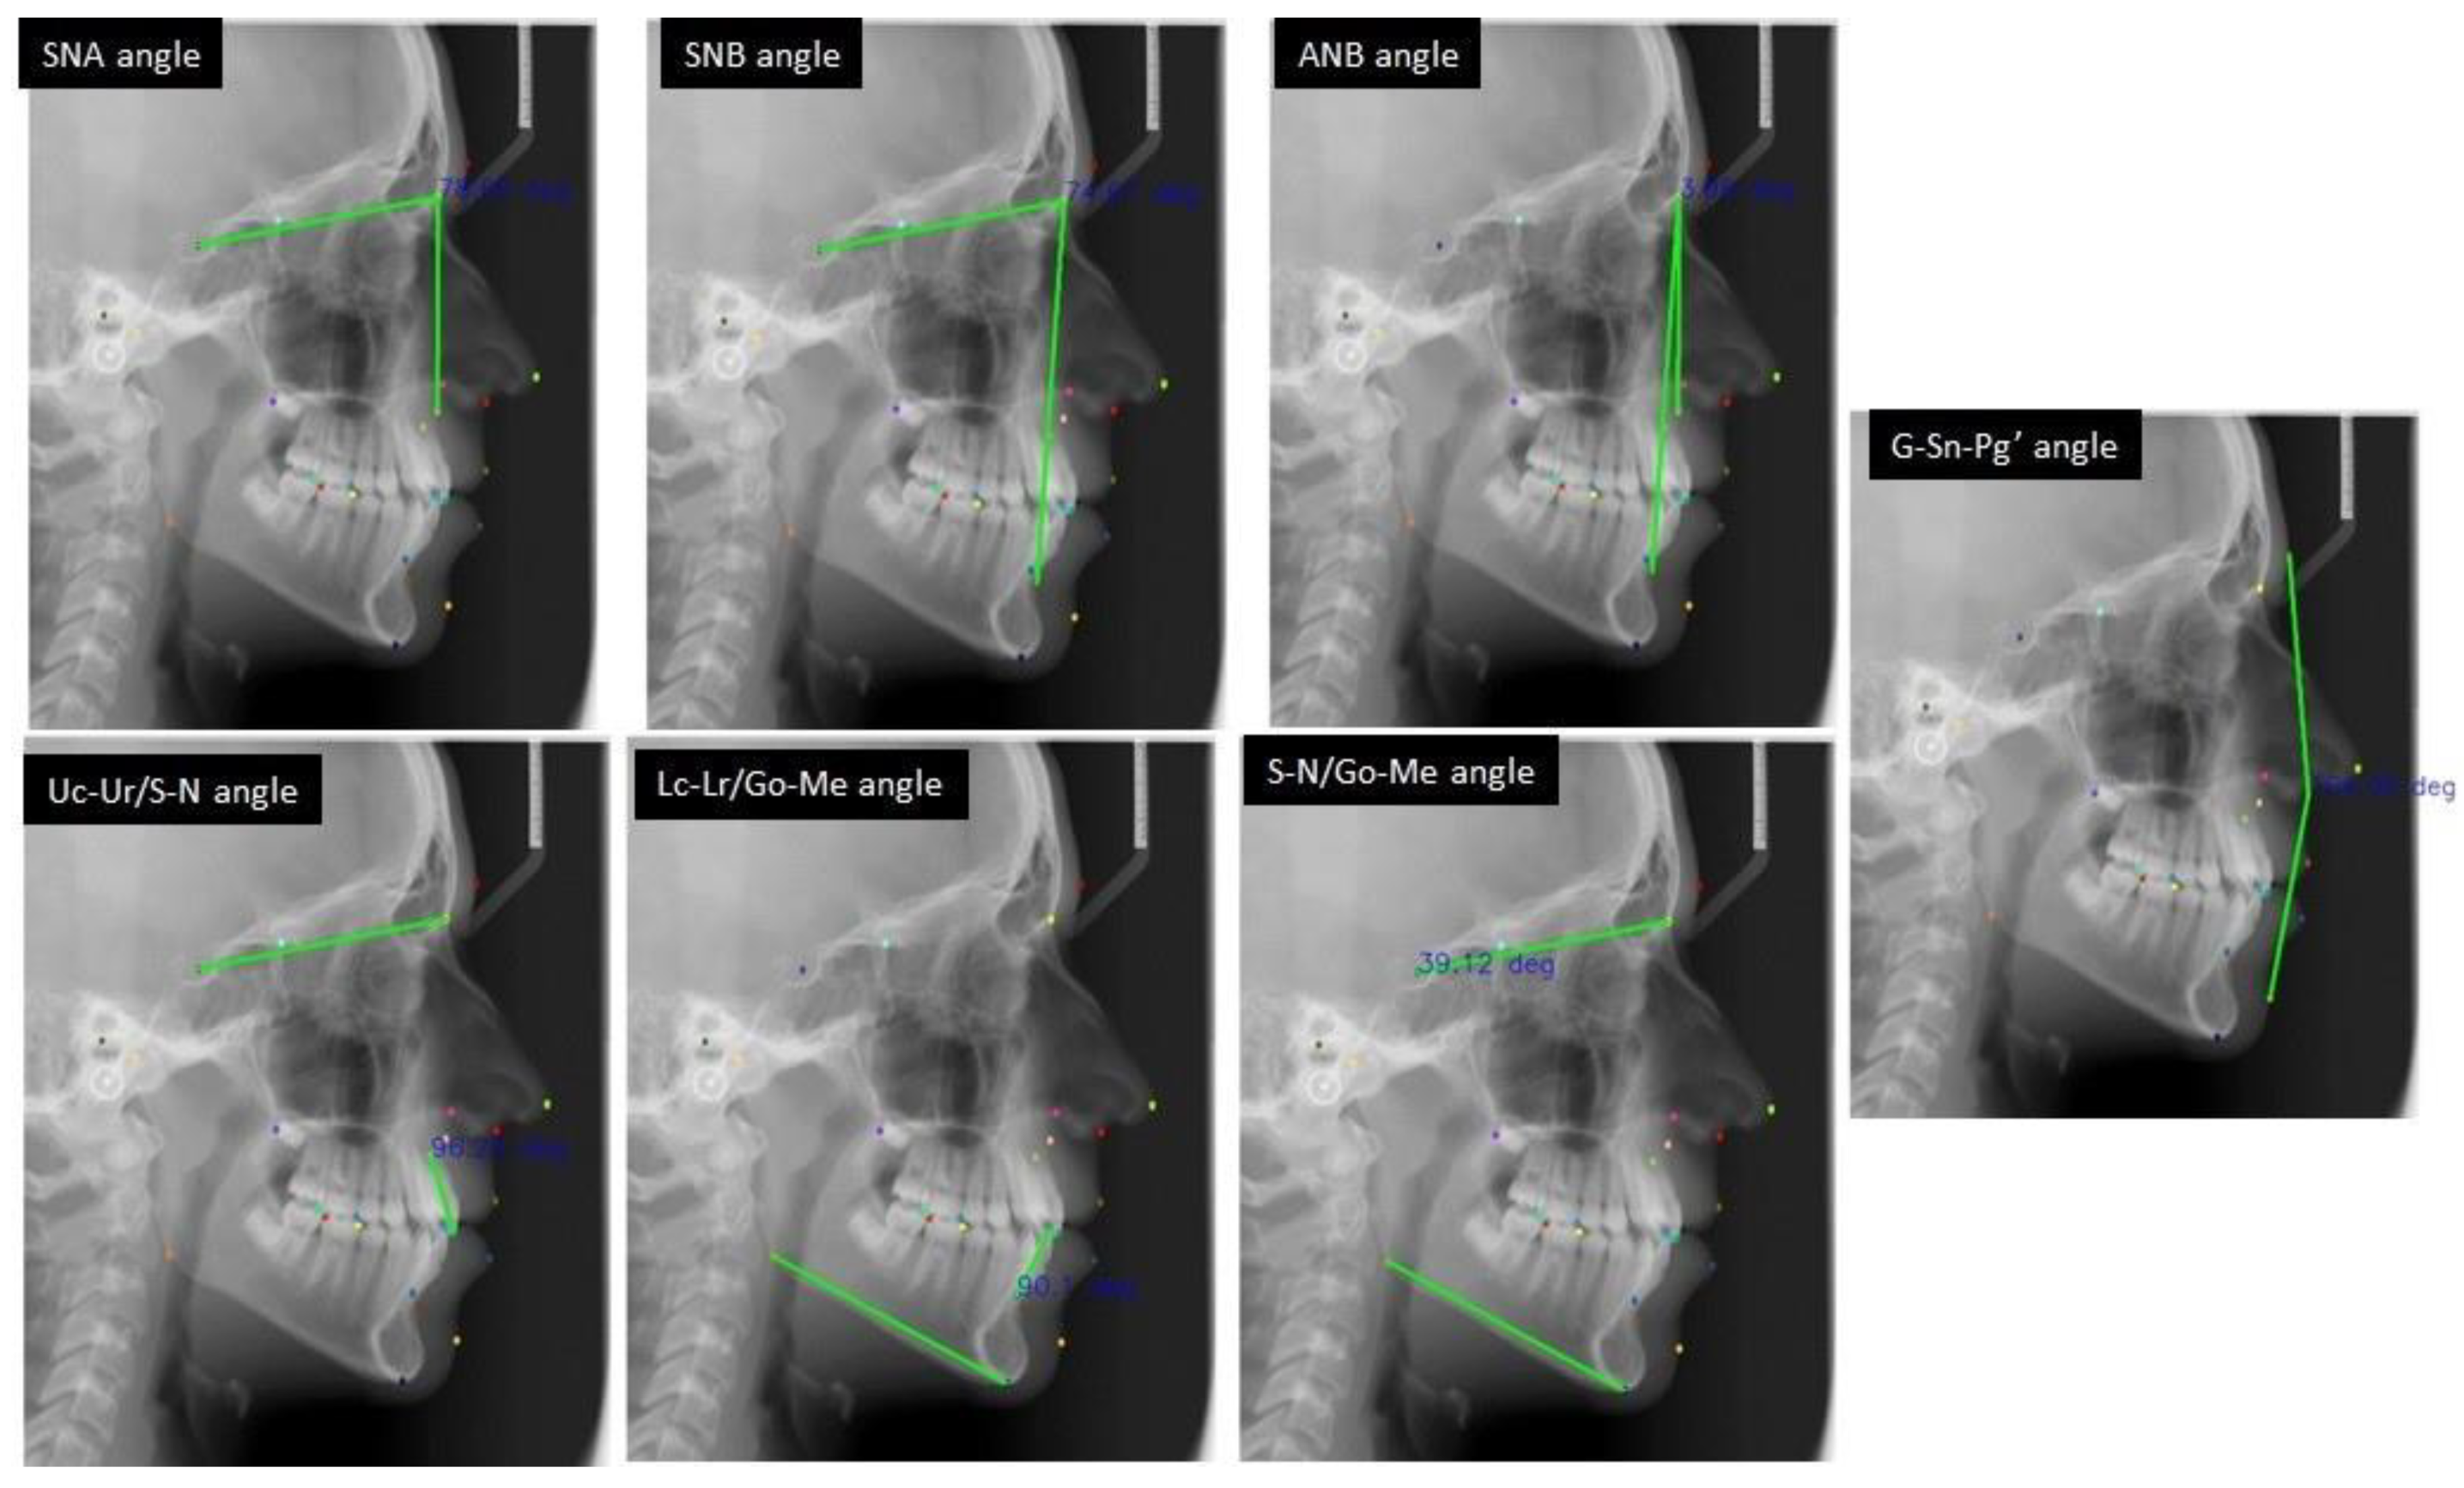

| Landmark | Description |

|---|---|

| S (Sella) | The geometric center point of the pituitary fossa. |

| P (Porion) | The most superior point on the external auditory meatus. |

| Go (Gonion) | Most posterior and inferior point on the curvature of the angle of the mandible. |

| N (Nasion) | The most anterior point on the frontonasal suture. |

| O (Orbitale) | The lowest point on the inferior rim of the orbit. |

| A (Point A) | The deepest point on the bony concavity between the ANS and supradentale. |

| B (Point b) | The deepest point on the bony concavity between the pogonion and infradentale. |

| Me (Menton) | The most inferior point on the hard tissue chin. |

| G (Glabella) | The most anterior point on the forehead. |

| Sn (Subnasale) | The junction of the nose and upper lip. |

| Ls (Labrale superius) | The most prominent point on the upper lip. |

| Li (Labrale inferius) | The most prominent point on the lower lip. |

| PgS (Soft tissue pogonion) | The most prominent point on the soft tissue chin. |

| Ur | The root tip of the upper incisor. |

| Uc | The crown tip of the upper incisor. |

| Lc | The crown tip of the lower incisor. |

| Lr | The root tip of the lower incisor. |

| ANS (Anterior nasal spine) | Anterior tip of the nasal spine. |

| PNS (Posterior nasal spine) | Posterior tip of the nasal spine. |

| U6M Upper first molar mesial tip | Most prominent point on the mesial cusp. |

| U6D Upper first molar distal tip | Most prominent point on the distal cusp. |

| L6M Lower first molar mesial tip | Most prominent point on the mesial cusp. |

| L6D Lower first molar distal tip | Most prominent point on the distal cusp. |

| SEM (Sphenoethmoidal point) | Intersection of the greater wing of sphenoid and the cranial floor. |

| Pn (Pronasale) | The most anterior point on the nose. |

| Co (Condylion) | The most superior and posterior point on the condylar head. |